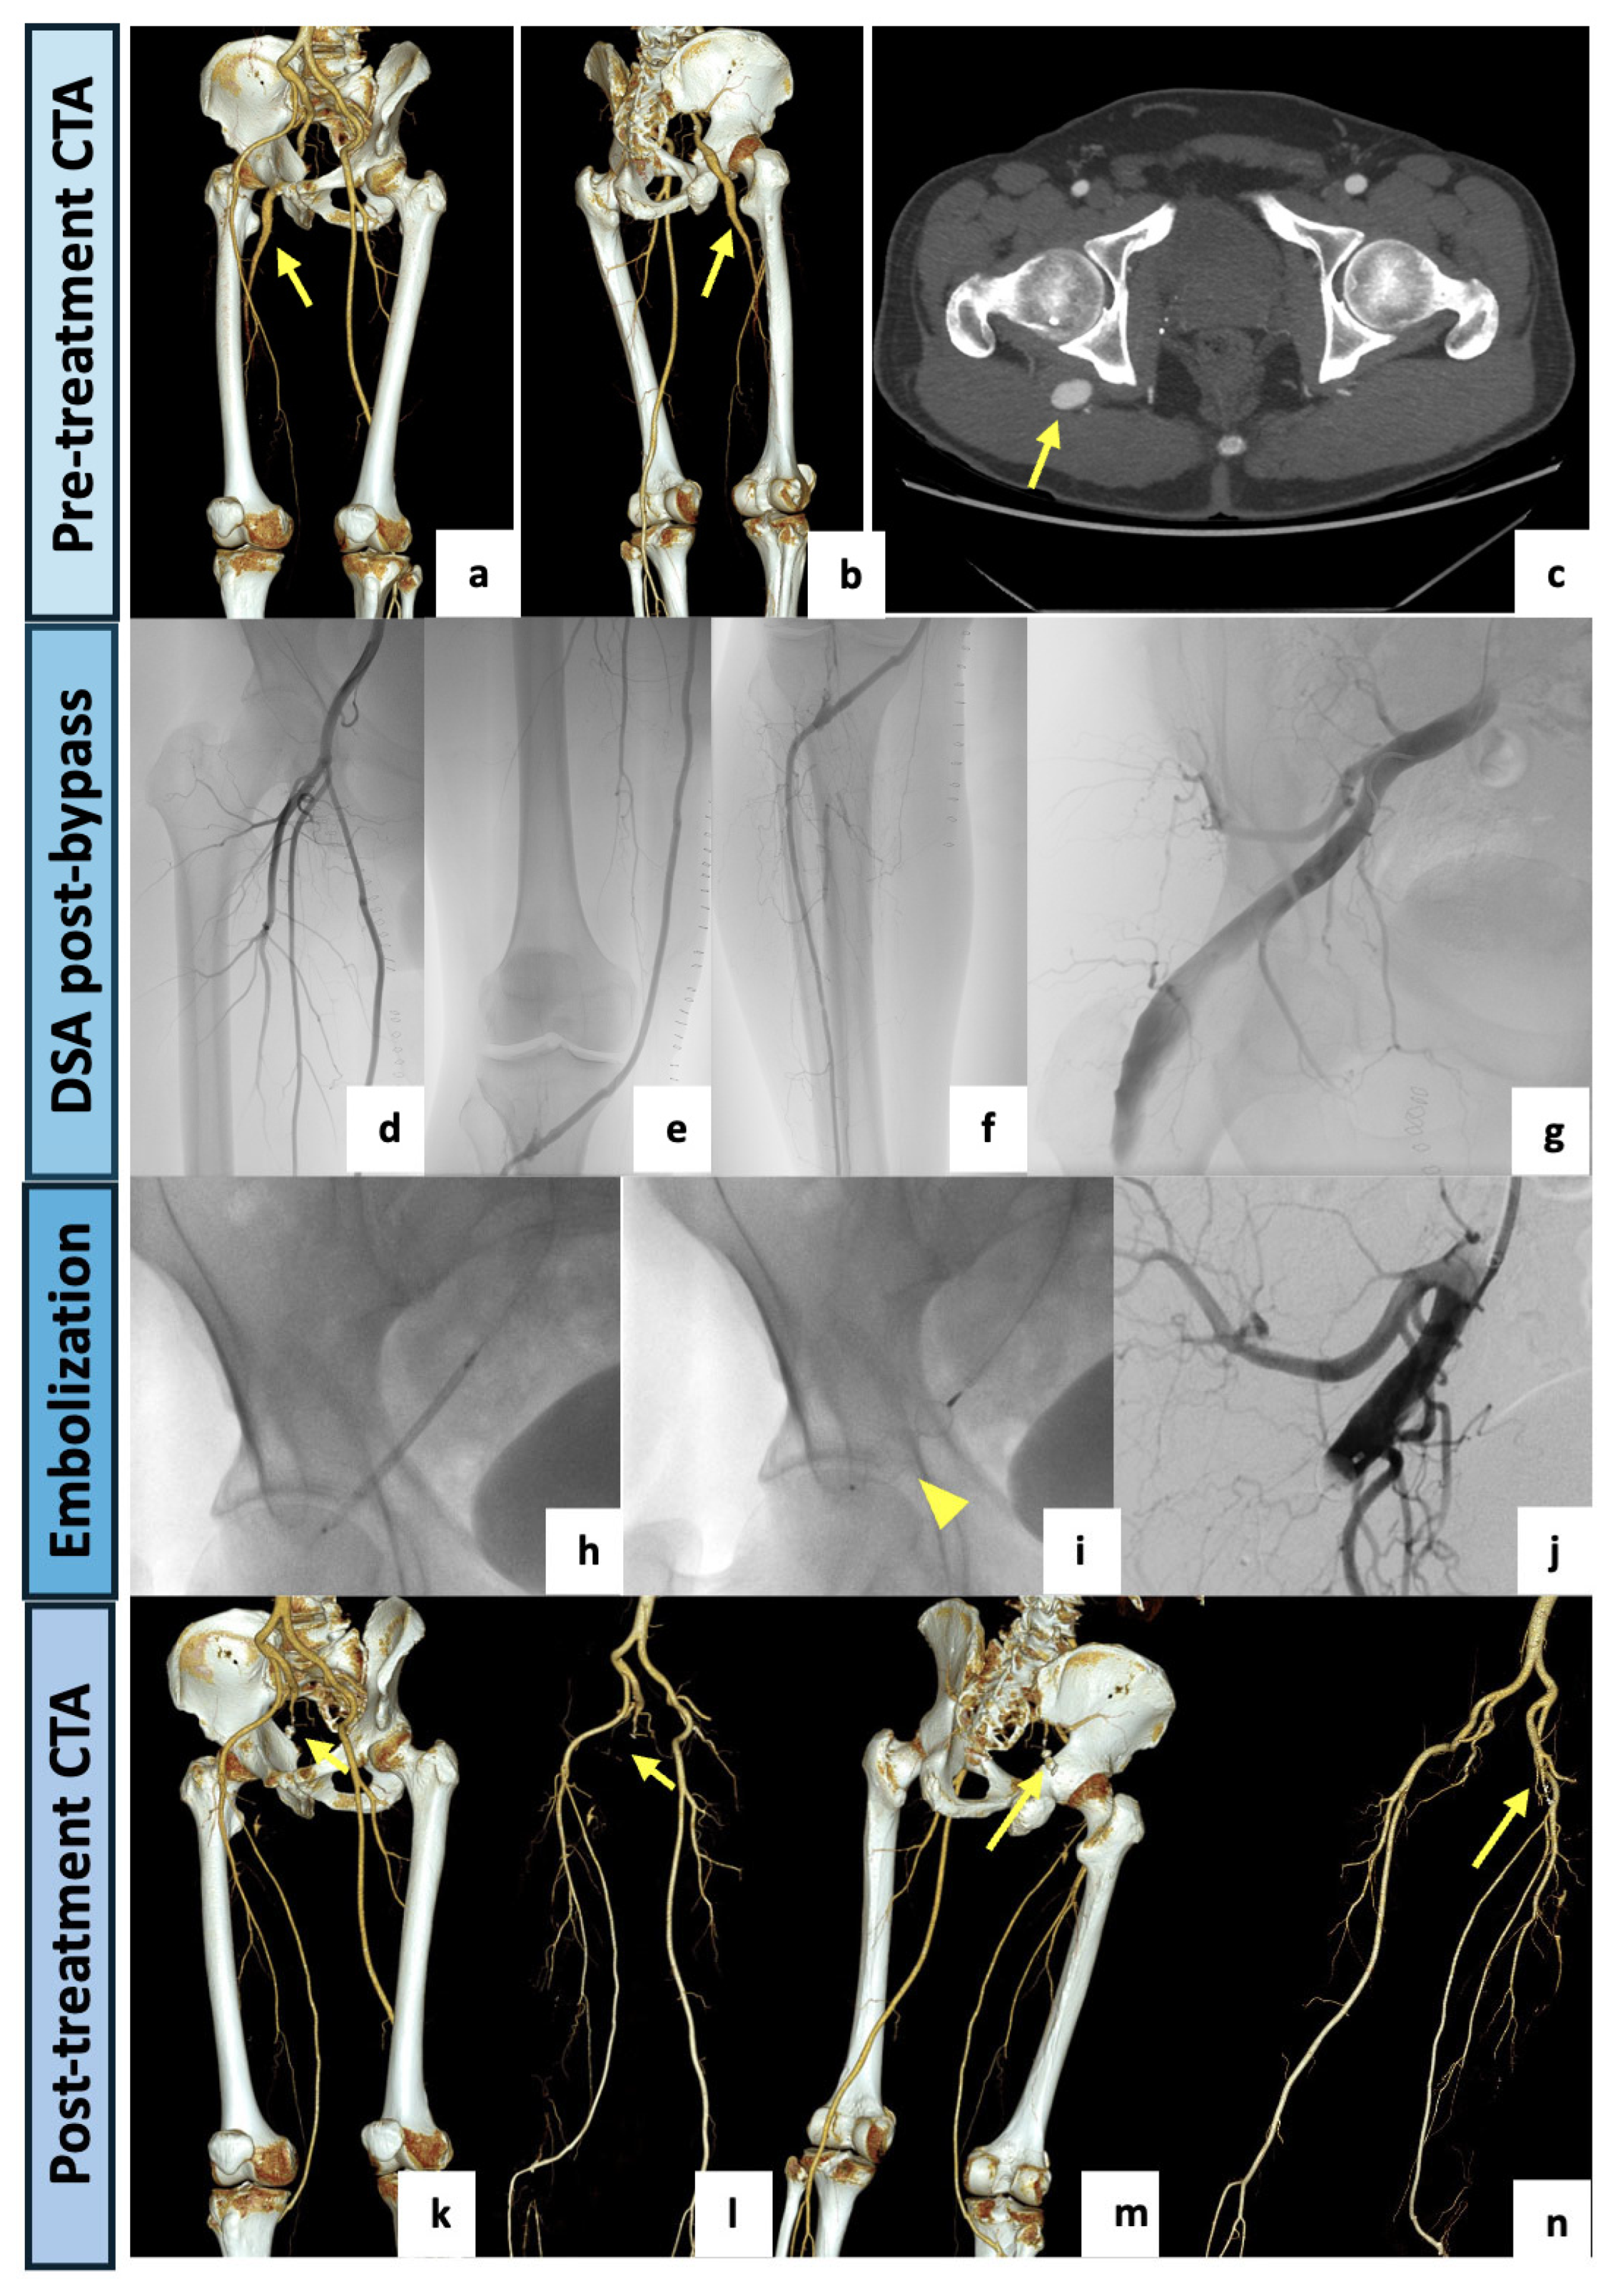

| 2 | 53 | Male | Critical ischemia with rest pain of the right lower limb | CTA | Right limb: Type 2a with aneurysmatic PSA | Hybrid approach: right femoral-tibial bypass and endovascular embolization of the aneurysmal PSA. | Clinical FU: symptoms improvement. CTA FU (3-month): patent bypass, completely excluded aneurysm. |